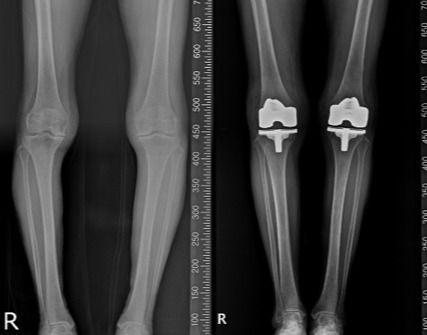

80세 여성 환자의 인공관절 수술 전후, 인공관절 수술은 정확한 삽입과 정렬이 중요하다. /연세사랑병원 제공 |